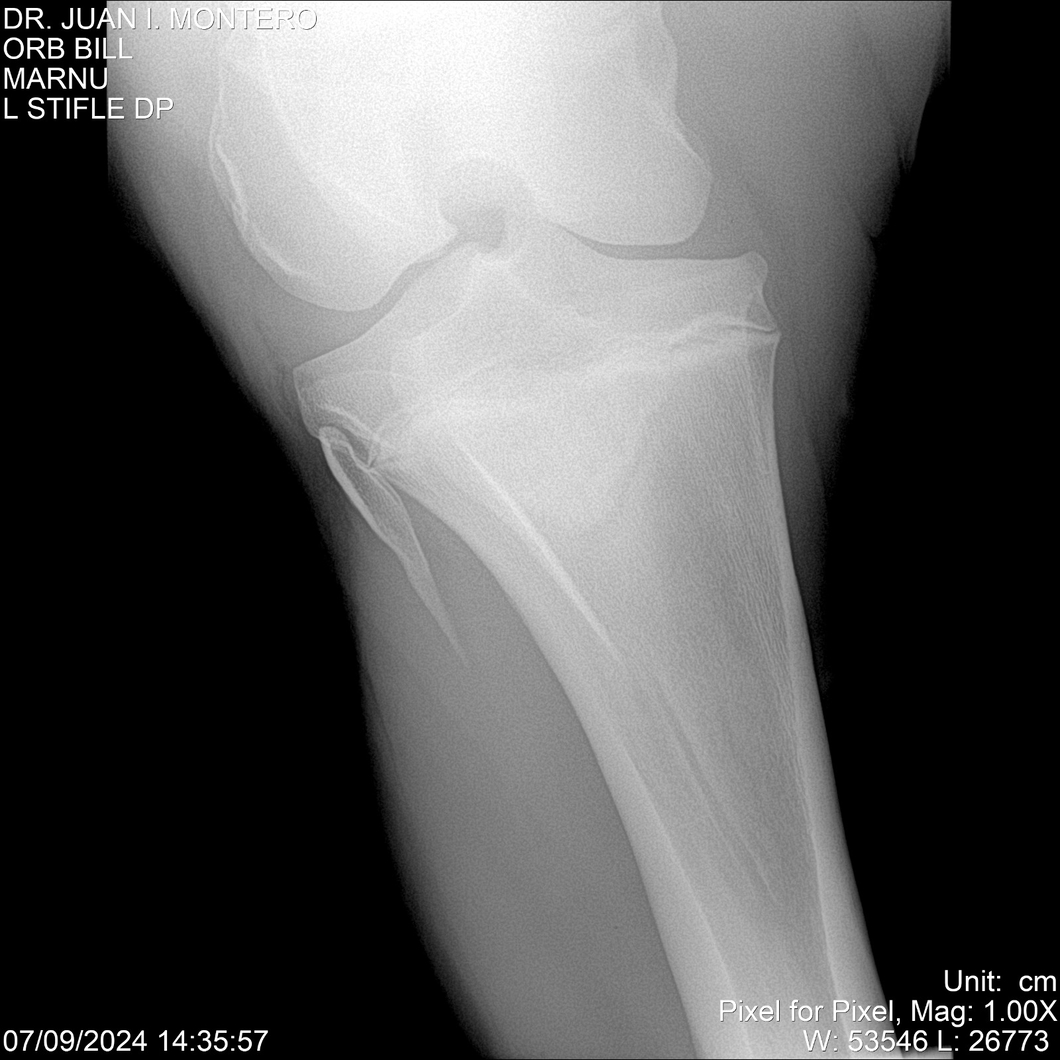

LOTE 7, ORB BILL 🔥 🔥 🔥 Lote Anterior Volver al remate Lote Siguiente Ficha Contacto Montevideo - Ficha del Lote Identificador: #282523 Categoría: Yeguarizos Montevideo - 83 Visualizaciones ClicData Contacto Empresa: Abelenda N. R., Walter Hugo Nombre*: Teléfono* : E-mail* : Mensaje Enviar Registrese gratis Este contenido Exclusivo está disponible sólo para usuarios registrados Ingresar